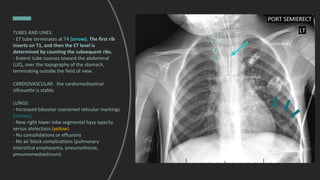

TUBES AND LINES:

- ET tube terminates at T4 (arrow). The first rib

inserts on T1, and then the ET level is

determined by counting the subsequent ribs.

- Enteric tube courses toward the abdominal

LUQ, over the topography of the stomach,

terminating outside the field of view.

CARDIOVASCULAR: the cardiomediastinal

silhouette is stable.

LUNGS:

- Increased bibasilar coarsened reticular markings

(arrows)

- New right lower lobe segmental hazy opacity

versus atelectasis (yellow)

- No consolidations or effusions

- No air block complications (pulmonary

interstitial emphysema, pneumothorax,

pneumomediastinum)